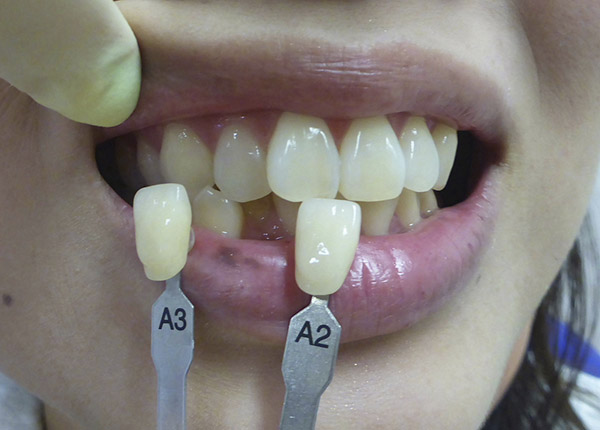

ホワイトニングの症例

症例01

ビフォー

アフター

症例02

この方は毎年、ホワイトニングをして数年、現在もご覧のような綺麗な歯をしております。